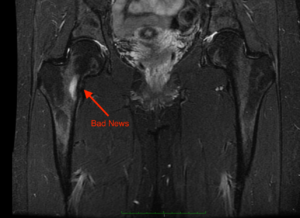

- Stress fracture of the hip joint:- stress fractures occur usually in bones that are fatigued. They are also called fatigue fractures. In active population, usually, stress fracture will develop as microfractures that don’t get a chance to heal because there is a small amount of bearable load being put on the hip continously. Additionally, if there is an imbalance between bone resorption and bone formation, then the chances of stress fractures are high.